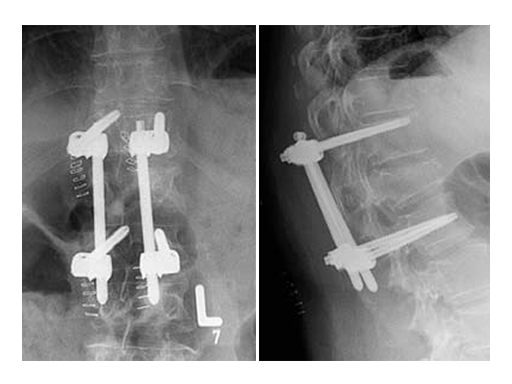

Based on the preoperative analysis and the surgical plan, the patient was positioned supine for the first surgery and the fracture was stabilized with a bridging construct (T12-L2) from posterior. Due to the ruptured disc, an anterior reconstruction of the spine was planned for a later stage surgery. The posterior stabilization was considered to be sufficient to bridge the fracture and time between both surgeries.

Using the USS Fracture MIS system for the initial stabilization allowed for a minimally invasive approach with intraoperative active reduction of the spinal fracture. The unique design of the fracture clamp allowed for independent correction of the sagittal alignment (Fig a) as well as height readjustment (Fig b).

For this patient, independent lordosis correction, height readjustment, and spinal stabilization were the primary goal of surgery. As percutaneous toploading pedicle screw systems cannot provide independent correction of the flexion-compression deformity, the fracture clamps and Schanz screws of the USS Fracture MIS system were used to overcome this disadvantage.

As a result of the ruptured disc and the fractured superior endplate, a hemivertebrectomy was performed and reconstruction was performed using an autologous iliac crest bone graft. To keep the graft in place and to allow for early posterior implant removal, an ArcoFix plate was used, allowing for slight compression as well as final sagittal reconstruction.

The hemivertebrectomy and the placement of the bone graft and ArcoFix plate were performed applying thorascopically assisted surgical technique.

Follow up CT Scans (AP, lateral and coronal) after the second surgery.